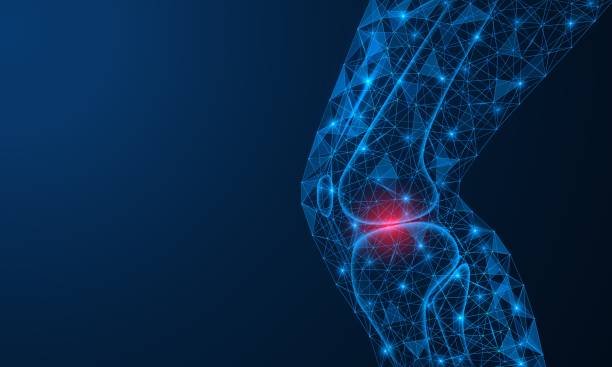

무릎 통증 원인 초기 치료 자세히 알아보기

무릎 통증이 초기에 발견되고 적절한 치료를 받으면, 심각한 상태로 악화되는 것을 예방할 수 있습니다. 무릎 관절은 몸의 중심부에 위치하고 있어, 무게 중심의 일부를 지지하며, 매우 복잡한 기구로 구성되어 있습니다. 따라서 무릎 관절의 이상은 다양한 원인과 증상을 보일 수 있습니다. 초기에 발견하여 조치를 취하지 않으면, 무릎 관절은 더 큰 문제로 발전할 수 있어 이번 시간에는 무릎 통증 원인과 초기 치료에 대해 알아보겠습니다.